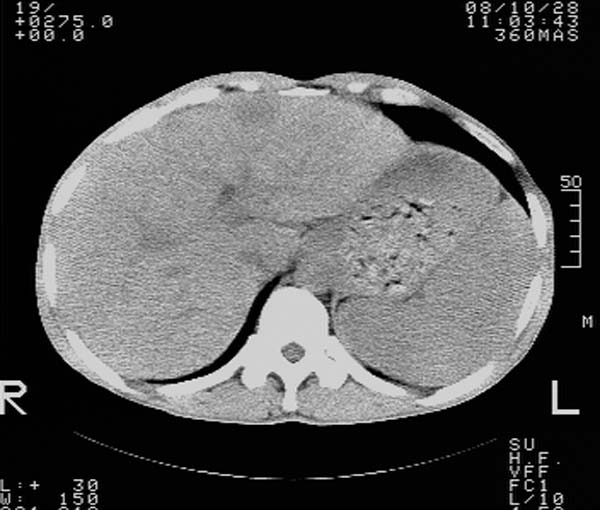

m,65y。半年前发现颈小结节,逐渐增多增大,现双侧耳后、颌下及颈部表浅淋巴肿大。胸片示双肺门增大。外院曾穿刺诊断为淋巴结核。在我科作胸腹部ct,我们觉得外院病检有误。现将图像上传请战友讨论。

纵隔内及腹膜后广泛淋巴结肿大,脾大,肝内似可见低密度影,结合病史半年前发现颈小结节,逐渐增多增大,现双侧耳后、颌下及颈部表浅淋巴肿大。考虑淋巴瘤。

我们也是首先考虑淋巴瘤。只是外院病检报告是结核。让人迷惑。肝左叶多发低密度占位,没增强不好定论。

纵隔,双肺门腹膜后多发淋巴结重大,非融合,肝脾轻度肿大,双肺野弥漫性小结节;考虑淋巴瘤,结节病可能性

纵隔内,双肺门、腋窝及腹膜后多发肿大淋巴结影,肺内小结节影,肝脾体积增大,支持淋巴瘤。肝内多发低密度影,考虑小囊肿。

考虑淋巴瘤肺、肝内转移,脾脏肿大。

纵隔内,双肺门、腹膜后多发肿大淋巴结影及颈部淋巴结肿大,肝脾体积大.结合临床,淋巴瘤可能性大。